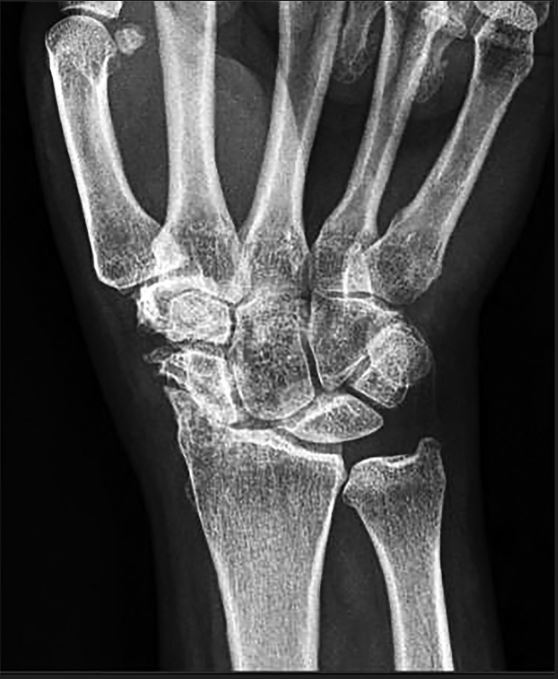

Basilar thumb OA:

1. Describe this radiograph.

This is a plain radiograph of the left hand in AP projection.

with joint space narrowing at the 1st CMCJ with sclerosis and osteophytes > 2mm. Mention also no STT arthritis noted (means not end stage).

**Plain radiograph i will order is AP, Lat and Robert’s view of the thumb.

• *2. What is your diagnosis? What are your differential diagnosis?**

• Basilar thumb arthritis = 1st carpo-metacarpal joint arthritis.

4. What classification will you use?

Eaton and Littler Classification of Basilar Thumb Arthritis

Stage I to IV: based on degree of degeneration and subluxation of the joint

Stage I- Slight joint space widening (pre-arthritis)

Stage II- Slight narrowing of CMC joint with sclerosis, osteophytes <2mm

Stage III- Marked narrowing of CMC joint with sclerosis, osteophytes >2mm

Stage IV-Pantrapezial arthritis (STT-ScaphoidTrapeziumTrapezoid involved)

** In this case, patient is Stage III